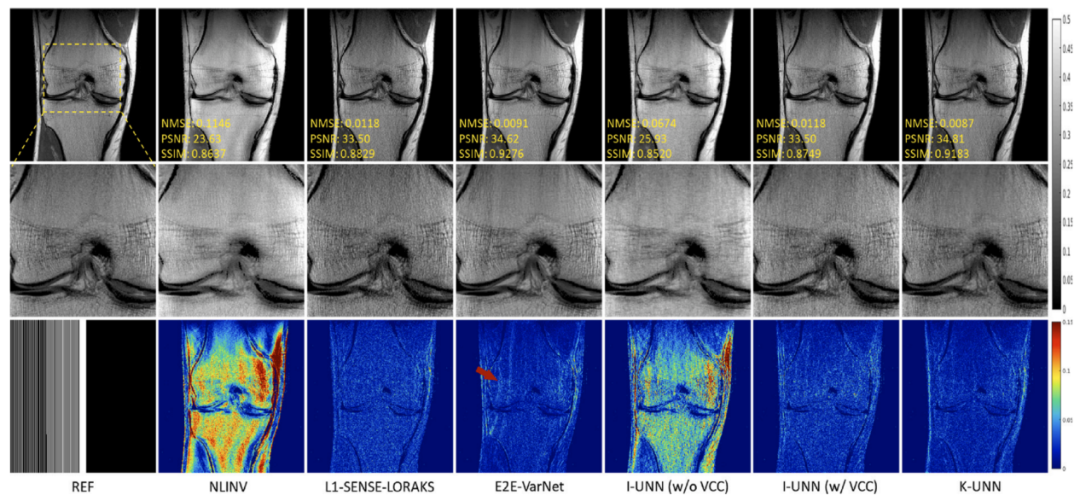

深圳先进院在高场快速磁共振成像研究获系列新进展

深圳先进院磁共振团队基于在深度学习快速磁共振成像领域的前瞻布局和深厚基础,针对当前技术需要大量训练样本及可靠性不足的问题,提出新型深度网络架构与模型,并充分结合磁共振成像独特的物理性质,实现高加速下的准确重建。

深圳先进院医学成像科学与技术系统重点实验室注重交叉利用数学和物理前沿,进行关键技术与系统的突破。快速磁共振成像技术是磁共振成像的关键共性技术,其数学本质是要求解一个高度病态反问题,准确求解困难,深度学习技术已经成为求解这一问题的主流工具。深圳先进院磁共振团队基于在深...